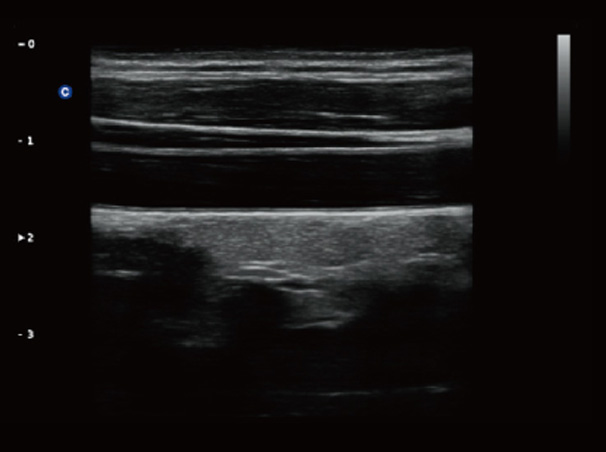

Chison Qbit 3 Color Doppler Digital Ultrasound Machine

Chison Qbit 3 A Slim Console Color Doppler System, Offers Ideal Patient Care With Its Easy Mobility, Smart Features, Significant Performance And Streamlined Workflow, To Strengthen The Clinical Confidence And Speed The Diagnostic Decision.

Chison QBit-3 Ultrasound Machine System, Offers Ideal Patient Care With Its Easy Mobility, Smart Features, Significant Performance And Streamlined Workflow, To Strengthen The Clinical Confidence And Speed The Diagnostic Decision.

- The Automat…Ma-Media Thickness Measurement For Mel Carotid Exam

- Providing The Mailed Result Of The In Kina Thickness, Help To Melted Me Diagnosis Automatically